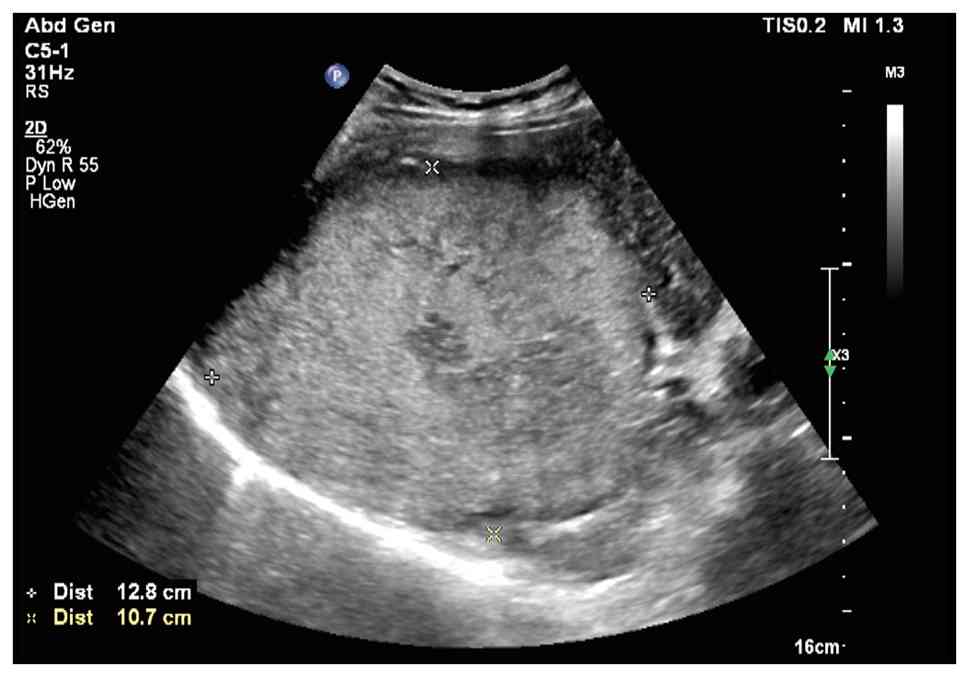

Ultrasound of the liver, gallbladder, pancreas, spleen and kidneys revealed a large solid mass in the liver (Fig. 1), a hypoechoic lesion between the upper pole of the right kidney and the posterior segment of the right lobe of the liver and a hypoechoic nodule in the first hepatic portal area. The liver ultrasound findings were consistent with chronic liver disease. An enhanced MRI of the liver suggested a high likelihood of hepatocellular carcinoma (HCC) in the right lobe (Fig. 2), with multiple metastatic tumors in the liver, bilateral adrenal glands and pancreas. A chest CT scan with three-dimensional reconstruction indicated a mass in the left hilum and left upper lobe of the lung, raising concerns for a malignant lesion with obstructive inflammation. The patient underwent ultrasound-guided biopsy of the liver mass and lymph nodes in the left supraclavicular region. Pathological examination (Fig. 3), supported by immunohistochemical staining performed according to the standard diagnostic protocols of the Department of Pathology at Hebei General Hospital, confirmed the diagnosis of SCNEC. Immunohistochemical staining (the full results are based on pathology reports rather than retrievable images, as the pathology reports cannot be published) included pan-cytokeratin (CKpan) (+), vimentin (−), chromogranin A (CgA) (+), synaptophysin (Syn) (+), cluster of differentiation 56 (CD56) (+), thyroid transcription factor-1 (TTF-1) (+), arginase-1 (−), hepatocyte paraffin 1 (HepPar-1) (−) and P53 (+++), and Ki-67 showing an active region of ~70% positive.

Case 1: Ultrasound image of the liver.

A large hyperechoic mass was identified in the right lobe of the

liver, measuring ~12.8×12.8×10.7 cm, with ill-defined borders and

heterogeneous internal echotexture.

Figure 1.

Case 1: Ultrasound image of the liver. A large hyperechoic mass was identified in the right lobe of the liver, measuring ~12.8×12.8×10.7 cm, with ill-defined borders and heterogeneous internal echotexture.